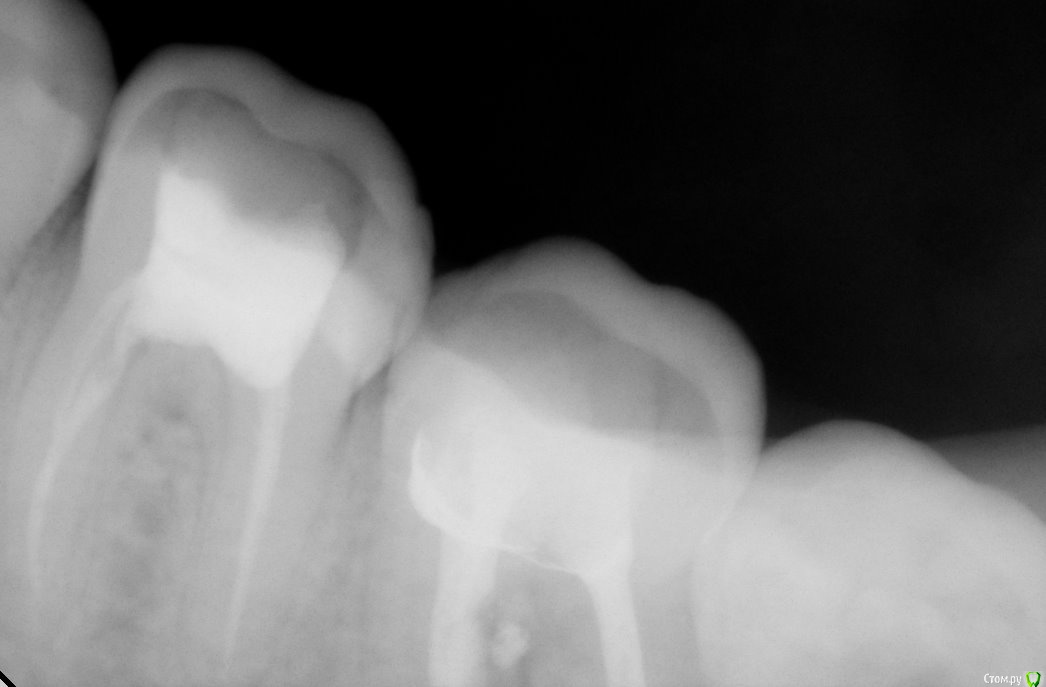

Jea Опубликовано 24 декабря, 2015 Поделиться Опубликовано 24 декабря, 2015 Добрый день! Помогите разобраться в сложившейся ситуации. Очень нужна оценка проведенного лечения сторонним экспертом. Хронология событий: 07.11 - первичный прием. Жалобы: ноющая боль в 7м левом нижнем зубе, носящая периодический характер, усиливающаяся в ночное время. Реакции на горячее/холодное, кислое/сладкое не было. Установленный диагноз: пульпит. Проведенные манипуляции: удаление нервов. 14.11- Пломбировка каналов. 21.11 - установка постоянной пломбы. 20.12 - повторное обращение по проведенному раннее лечению. Жалобы: боль после лечения не проходящая в течении месяца (нояющая, усиливающаяся в ночное время, при надкусывании). Есть левой стороной я не могла. Диагноз: воспалительный процесс в зубе. Манипуляции: распломбировка каналов, закладка лекарства, временная пломба. В течение 2х дней сильные постпломбировочные боли. Вечером 22.12 опухла десна. 23.12 прием по осложнениям после лечения, в ходе которого выяснилось, что во время распломбировки каналов зуб треснул и внесенное в канал лекарство вылилось в десну. Предложенный план лечения: удаление+ имплантация. Необходима оценка качества проведенного лечения и прогноз на дальнейшее лечение зуба. Прикрепляю все снимки, сделанные в ходе лечения. Благодарю! Ссылка на комментарий

Jea Опубликовано 24 декабря, 2015 Автор Поделиться Опубликовано 24 декабря, 2015 Мне надо понять, зуб треснул в результате некачественного лечения? А также действительно ли он треснул (видно ли это на снимках)? Необходима ли была распломбировка каналов? КАк вообще были запломбированы каналы? Ссылка на комментарий

St. Опубликовано 24 декабря, 2015 Поделиться Опубликовано 24 декабря, 2015 А также действительно ли он треснул (видно ли это на снимках)? Да, похоже на то. Ссылка на комментарий

red_butler Опубликовано 25 декабря, 2015 Поделиться Опубликовано 25 декабря, 2015 Как скоро мне необходимо удалить зуб? если в настоящее время зуб не беспокоит, то отложите решение на после праздников. В Вашем случае возможна одномоментная имплантация. А также по поводу соседней 6ки. Надо ли перелечивать каналы? Если да, то что ставить: пломбу или коронку? как минимум нужна ревизия корневых каналов и в дальнейшем коронка. 1 Ссылка на комментарий